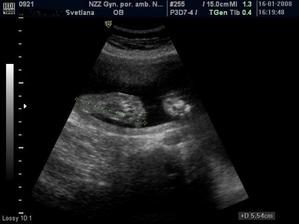

Sophie a veci okolo nej..ako ide cas a co sa deje

Mix fotiek 🙂